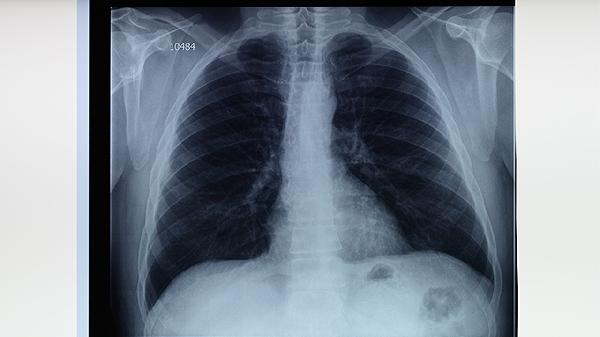

治療期間每月需進行痰涂片檢查、胸部X線復查及肝腎功能檢測。治愈后第一年每3個月復查一次,之后每年隨訪。糖尿病患者、HIV感染者等高風險人群需延長監(jiān)測周期。